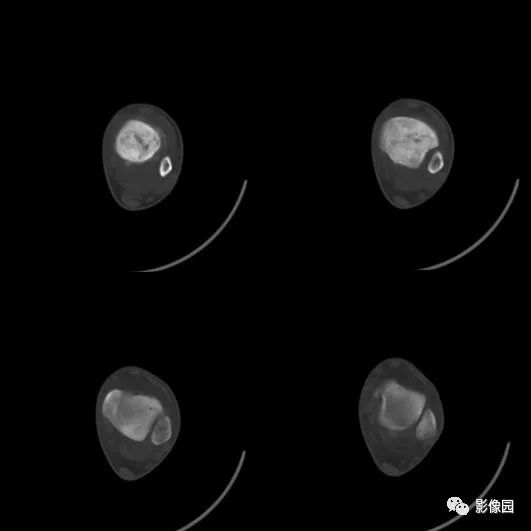

【影像学检查】2016-01-05

评论:前片X线示左胫骨下段及干骺端病变,髓腔内密度不均匀增高,内侧骨皮质可见骨质破坏,可见骨膜反应。CT示病灶内见多发斑片状肿瘤骨(黄色箭头),周围可见针状骨膜反应(红色箭头)。周围软组织肿胀。MRI示胫骨下段以长T1、长2信号为主的混杂信号影,未跨越胫距关节面,周围未见明显软组织肿块。周围软组织广泛片状长T1长T2信号影。复查X线示病变较前片明显进展,左侧胫骨远段及干骺端骨质破坏,周围可见针状骨膜反应及Codman三角(蓝色箭头)形成。相邻左侧腓骨下端、距骨滑车受累。

绝大多数骨肉瘤可依据X线平片确立诊断,但CT或MRI是必不可少的补充。MRI能清楚了解肿瘤侵及的范围,提供肿瘤周围血管、神经、肌肉受累的信息,有利于治疗方案的确立。CT除了与MRI一样有利于发现平片上不易显示部位的病变外,由于其对细小骨化和钙化敏感,当平片上不能肯定有无瘤骨或瘤软骨钙化时,CT对确定骨肉瘤的诊断有重要意义。